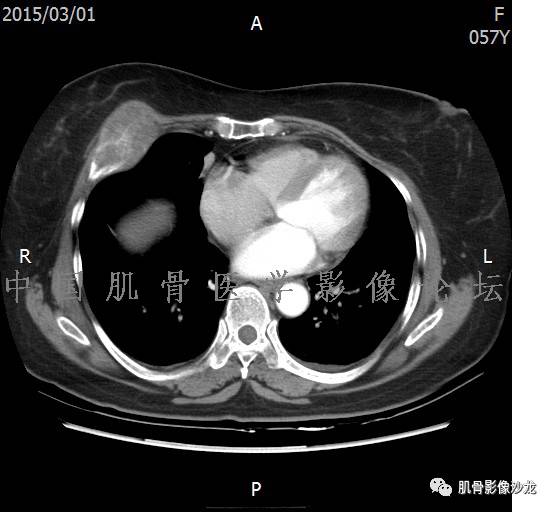

患者于2月前无明显诱因下出现腰骶部疼痛,夜间为重,逐渐加重伴左下肢麻木、疼痛,并有行走活动受限,在我院就诊,摄腰椎及骶髂部CT提示:腰椎骨质退变,腰3-4、4-5椎间盘膨出,骶髂关节炎。自用非甾体抗炎药无好转,再次来院就诊,门诊拟“骶髂关节炎”收住我科。病程无间歇性跛行,大小便正常。

专科检查:神清,脊柱无侧弯后凸畸形,椎体各节段无压、叩痛,双侧棘突旁无压痛,双侧骶髂关节压痛明显,左下肢放射痛,浅感觉较健侧减退,腰椎前屈后伸活动受限,膝、跟腱反射正常。

辅助检查:腰椎及骶髂部CT提示:腰椎骨质退变,腰3-4、4-5椎间盘膨出,骶髂关节炎。

雪舞 :第二例,位于骶骨,有骨质破坏并有软组织肿块,软组织肿块边界清

雪舞 :第二例挺难的,骨质破坏是溶骨性的,局部皮质中断,软组织肿块外缘光滑